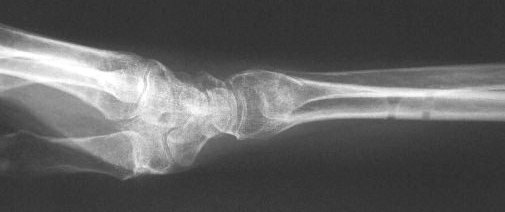

Clinical Example: Distraction plate fixation distal radius fracture

distal radius fracture